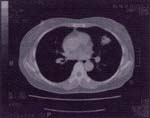

現在、わが国における部位別のガンの死亡率は、肺癌が胃癌を抜いて一位になっており、その数は年間5万人 以上にもなっています。その原因として、多くの肺癌が発見された時点で進行癌であり、その5年生存率 (5年後に生存している確率)が10%と低いことが上げられます。一方、1~2cmの早期癌であれば、そのほとんどが治る といわれていますが、単純X線による検診では発見が困難で、十分な成果が上がっていないのが現状です。 当院に設置されている64列CTは、早期の微小な肺癌を発見することが可能であり、 肺癌による死亡を予防できる最も手段とされています。多くの方々に、この機器によるドックを利用していただきます ようにお勧めいたします。